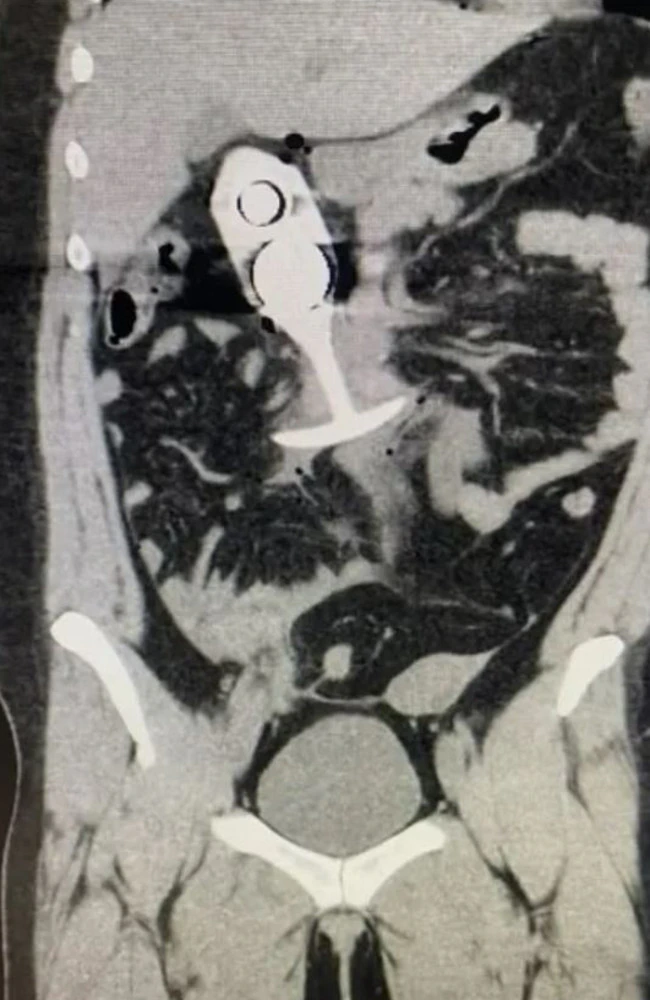

Rump Rocket

So ,, a 23 yo Australian woman goes in for an MRI scan , they tell her that she cannot have any meta..

By: